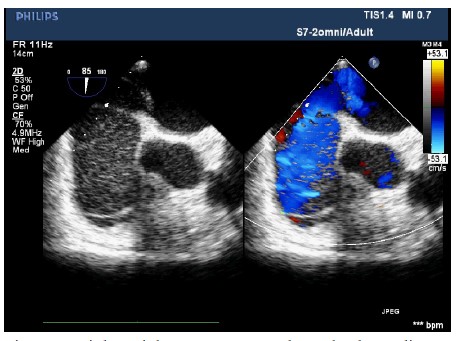

The patient entered the operating room and her ECG was monitored regularly. The induction of anesthesia was smooth. When the surgical team was manipulating the fracture, her blood pressure (BP) suddenly decreased to 63/43 mmHg, heart rate increased to 112 beats/min, and the saturation of pulse oxygen (SpO2) fell to 72%. 1 mg methoxamine was used to raise the blood pressure without success. 2 mg methoxamine, 6 mg ephedrine, and 8 μg nonadrenaline were subsequently given without significant blood pressure change. The central venous pressure was 15mmHg. In addition, the end tidal carbon dioxide decreased to 10 mmHg. There were no significant airway pressure changes. While an allergic reaction was initially suspected, no dermatological changes were identified. Emergency blood gas indicated a partial pressure of artery carbon dioxide (PaCO2) of 77.9 mmHg, and an oxygen partial pressure of 67mmHg. Potential pulmonary embolism was suspected. A transesophageal echocardiography (TEE) was followed. It revealed an enlarged right atrium (Figure1), hypokinesia of the free right ventricle wall, and poor filling of left ventricular. The ratio of left/right ventricular apparent disorder and the pressure of tricuspid valve was 51mmHg with massive regurgitation of 3.57m/s (Figure 2). Severe tricuspid reflux was also observed (Figure 3). Epinephrine and milrinone along with high-dose vasopressin were initiated. While no thrombi in the pulmonary or right ventricle were identified, unstable hemodynamics, changes in carbon dioxide, findings in TEE strongly suggested a possible major PE. Extracorporeal membrane oxygenation (ECMO) was immediately established and an emergent pulmonary thromboembolectomy was successfully performed. The patient was transferred to the surgical intensive care unit for monitoring and evaluation. The patient was discharged without residual deficits after 20 days in surgical intensive care unit.

Figure 1: Right atrial on 2D-transesophageal echocardiography. Enlarged RA and hypokinesia of the free right ventricle wall were observed.